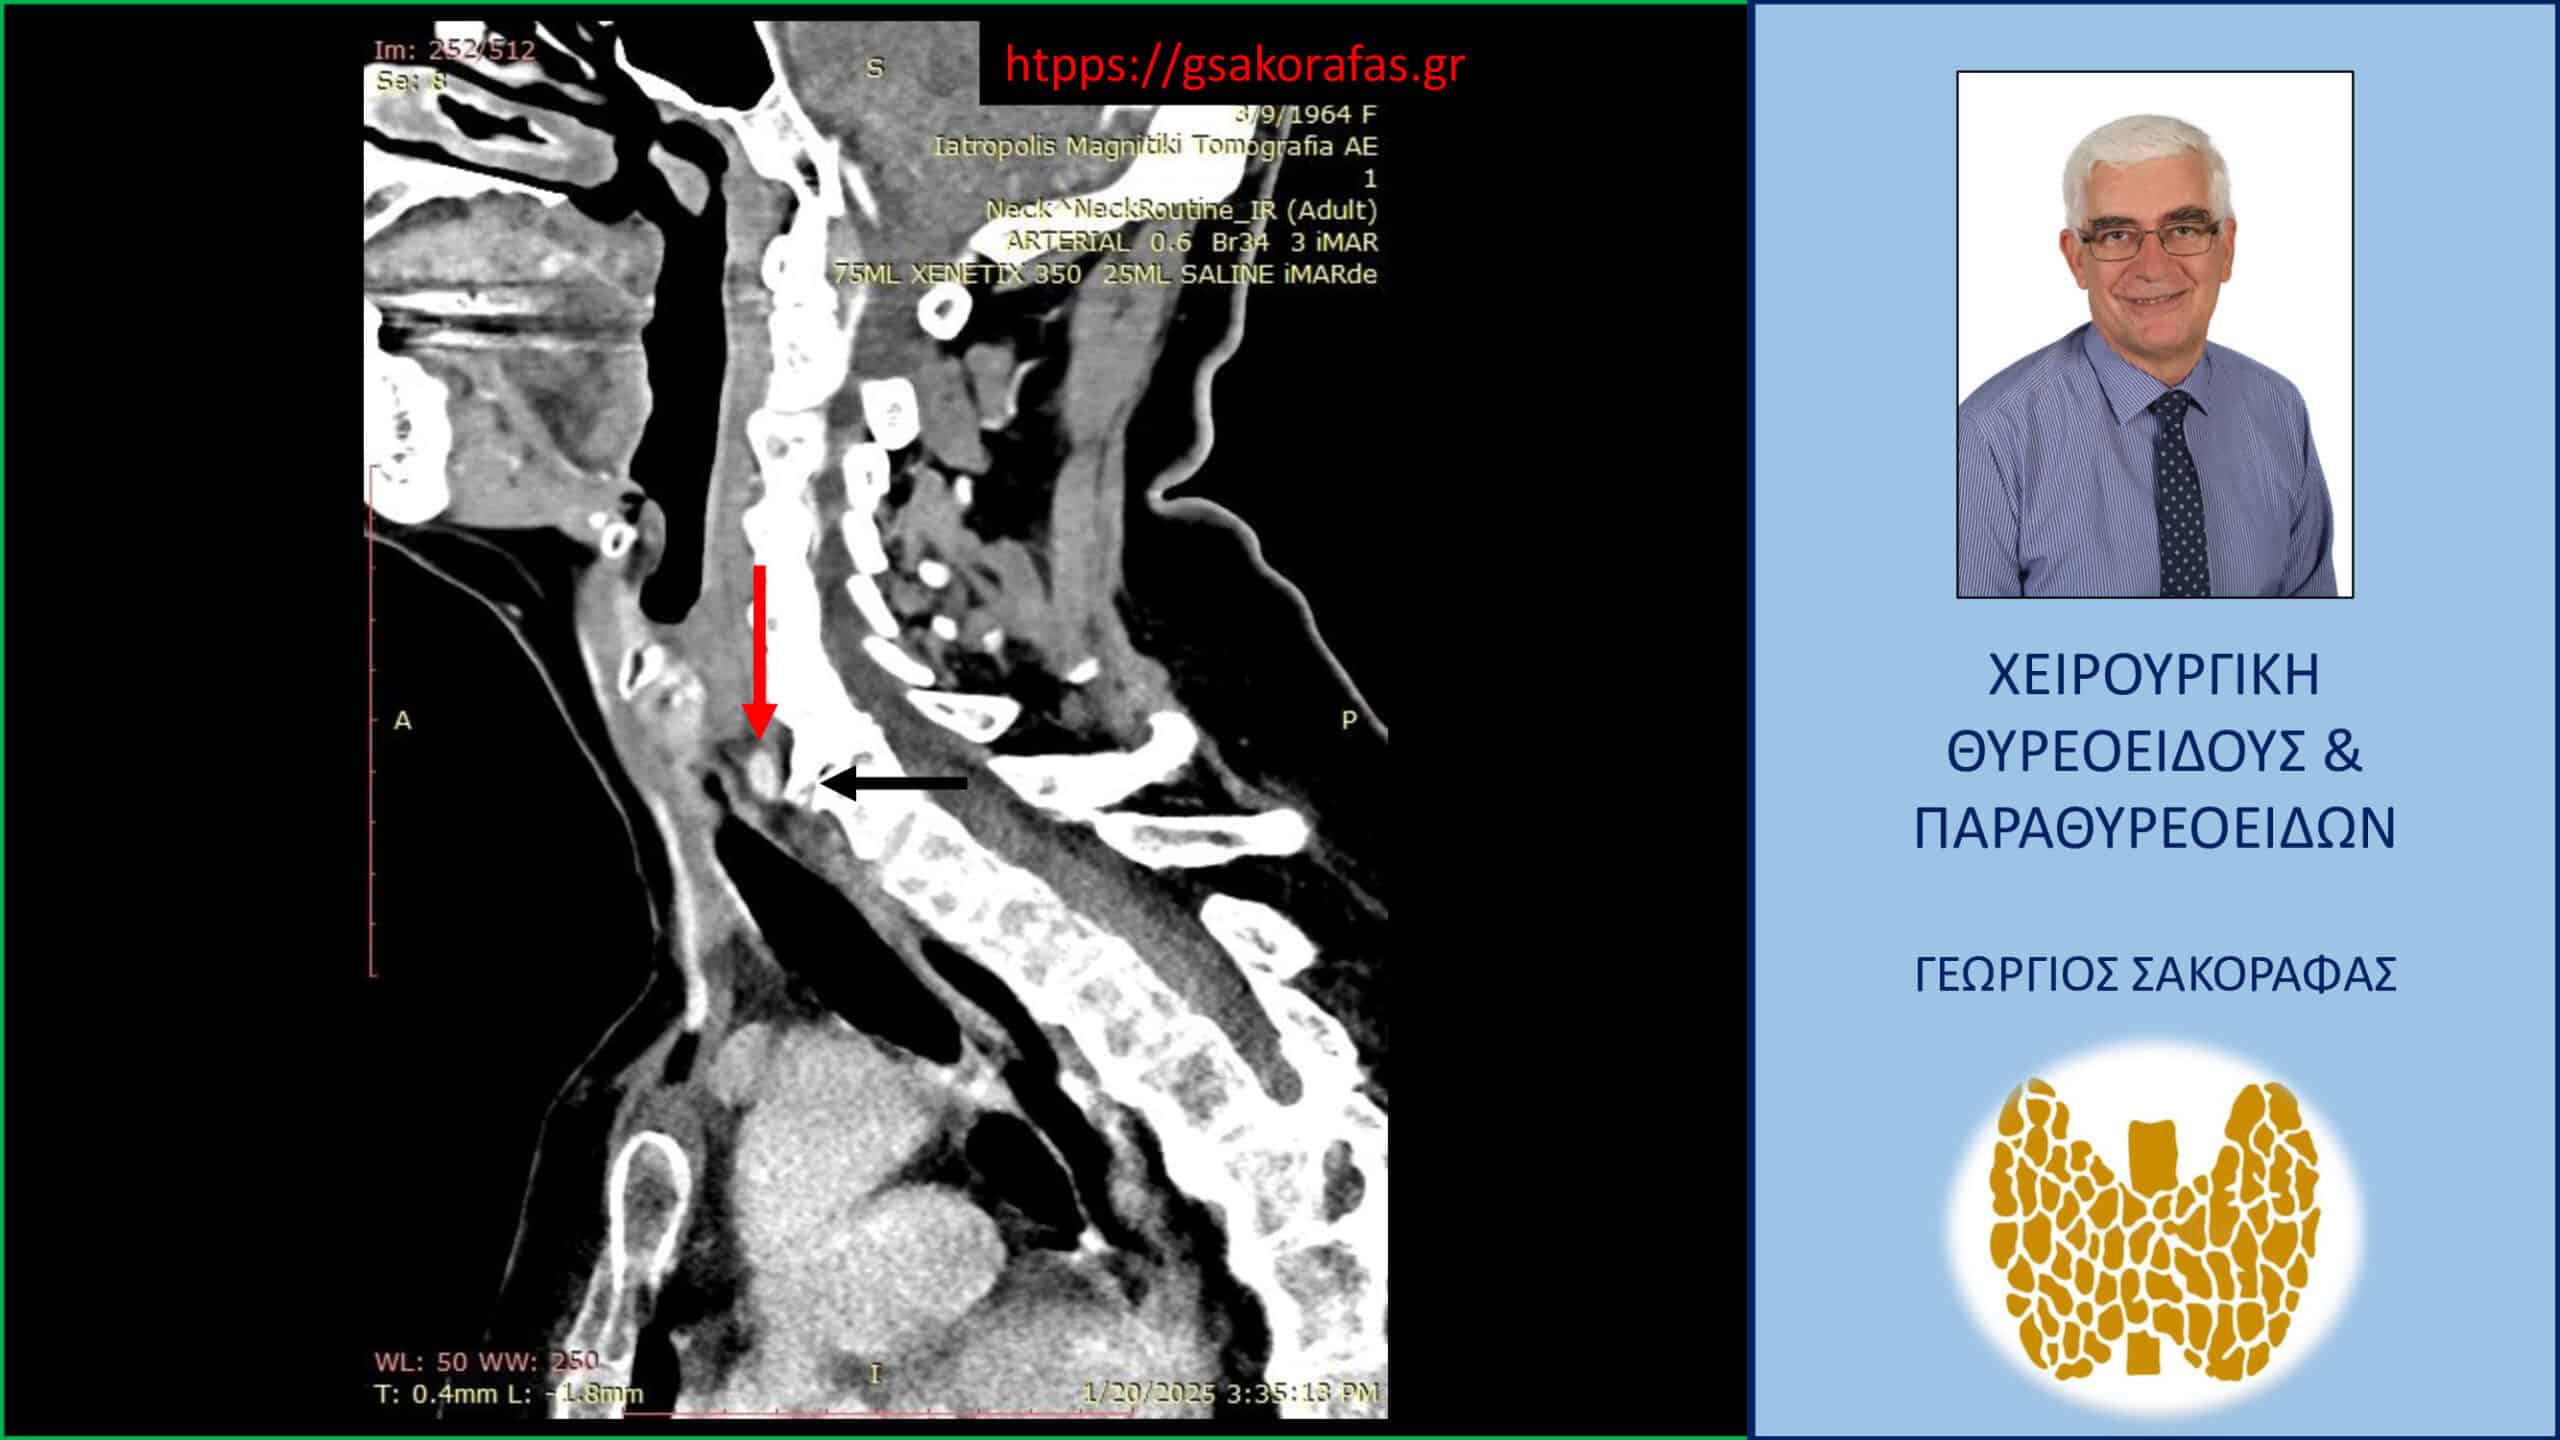

Έκτοπο αδένωμα παραθυρεοειδούς (κόκκινο βέλος)- απεικόνιση στην 4D-CT (προσθιοπίσθια διατομή). Το αδένωμα βρίσκεται σε επαφή με την προσπονδυλική περιοτονία (μαύρο βέλος)

Λόγω επιμένοντος PHPT και με δεδομένους τους περιορισμούς των δύο βασικών διαγνωστικών εξετάσεων (υπερηχογράφημα και σπινθηρογράφημα) παραπέμφθηκε για περαιτέρω έλεγχο με τετραδιάσταση αξονική τομογραφία (4D-CT) όπου περιγράφεται μόρφωμα με διαστάσεις 9 x 7.5 x 5 mm παρά τον οισοφάγο, σε επαφή με την προσπονδυλική περιτονία, στο ύψος του Α6 σπονδύλου, πίσω από την τραχεία και την δεξιά κοινή καρωτίδα.

H εικόνα είναι συμβατή με έκτοπο αδένωμα παραθυρεοειδούς.